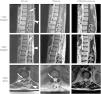

Materials and methodsA literature review of cases of spinal angiolipoma was performed. In addition, two of the cases encountered in our practice are presented. The first case refers to a 35-year-old male patient with a history of spinal fusion because of a T9 fracture, while the second concerns a 46-year-old male patient with an epidural mass extending outside the spinal canal, who underwent fine needle biopsy and embolisation of its feeding vessel.